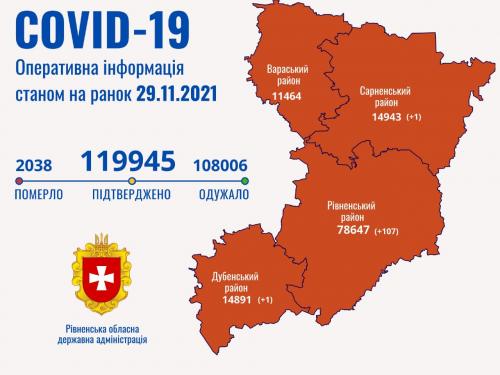

Пів тисячі - у важкому стані, 9 жителів Рівненщини померли за добу від коронавірусу